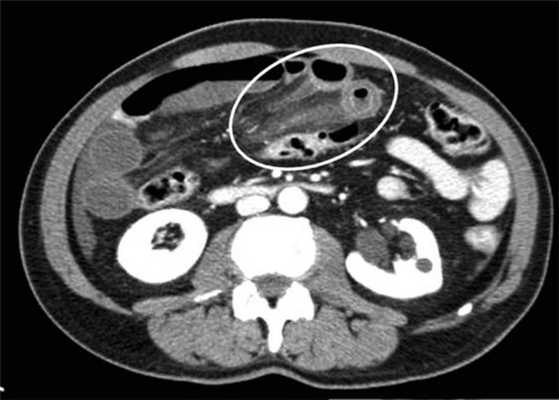

(а) При КТ с контрастированием в аксиальной проекции выявлена транспозиция верхней брыжеечной артерии (указатель) и вены (стрелка).

(б, в) На более низких уровнях при КТ в аксиальной проекции выявлен симптом «водоворота» (стрелка), представляющий собой перекручивание верхней брыжеечной вены и ее ветвей, брыжеечного жира и петель кишки вокруг верхней брыжеечной артерии по часовой стрелке.

(г, д) На рентгенограммах выявлен симптом «штопора» — спиральная конфигурация 4-го отдела двенадцатиперстной кишки и проксимальной части тощей кишки.

Перекручивание тонкой кишки, приводящее к ее завороту, может быть вызвано различными причинами, такими как врожденная мальротация средней кишки, анатомические аномалии, воспалительный процесс и опухоли. Врожденный заворот кишечника обычно обнаруживают в первые месяцы жизни, он характеризуется патогномоничными визуализационными проявлениями, включающими симптом «штопора» и симптом «водоворота».

б) Лучевая диагностика заворота тонкой кишки. При стандартной рентгенографии чаще выявляют неспецифические признаки, и она редко бывает информативной в диагностике. Симптом «штопора», известный как диагностический признак заворота средней кишки, отображает спиральную конфигурацию 4-го сегмента двенадцатиперстной кишки и проксимальной части тощей кишки, классически выявляемую при рентгенографии у детей, особенно у младенцев. Его можно визуализировать в переднезадней и боковой проекциях.

Ультрасонография (УС) информативна при патологическом перекручивании верхних брыжеечных артерии и вены (симптом «водоворота»), выявляемом при цветном допплеровском картировании. Однако зависимость от мастерства исследователя, а также газ в тонкой кишке, мешающий исследованию верхних брыжеечных сосудов, часто ограничивают диагностическую пользу. КТ стала важным методом визуализационной диагностики, особенно при завороте тонкой кишки у взрослых. Как и при УС, характерным признаком при КТ служит симптом «водоворота», который возникает в результате перекручивания верхней брыжеечной вены и ее ветвей, брыжеечного жира, кишки и ветвей верхней брыжеечной артерии вокруг самой верхней брыжеечной артерии, чаще по часовой стрелке.